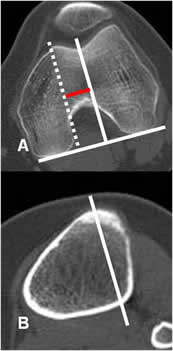

Angulo de rotación de la rodilla:

Medido mediante TAC, con cortes axiales que se superponen. Uno sobre los cóndilos femorales y otro sobre la tuberosidad tibial. (22).

El ángulo se forma por las líneas bicondilea posterior y otra que pasa por la parte

posterior de la epífisis tibial. El valor normal es de 5º. (3, 18, 22). (Fig 78 y 79).

Fig 78. Rotación de la rodilla.

A: TAC axial, con línea que pasa por la parte posterior de los cóndilos femorales.

B: TAC axial a nivel de la espina tibial y se traza la línea que pasa por la parte posterior de la tibia.

Se superponen y forman el ángulo de rotación de la rodilla.